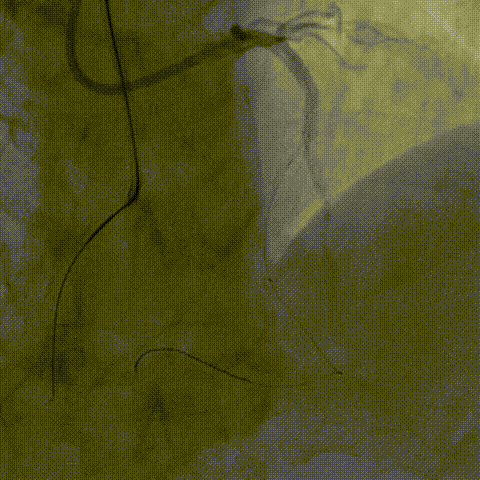

术后IVUS

术后造影

复查左冠造影